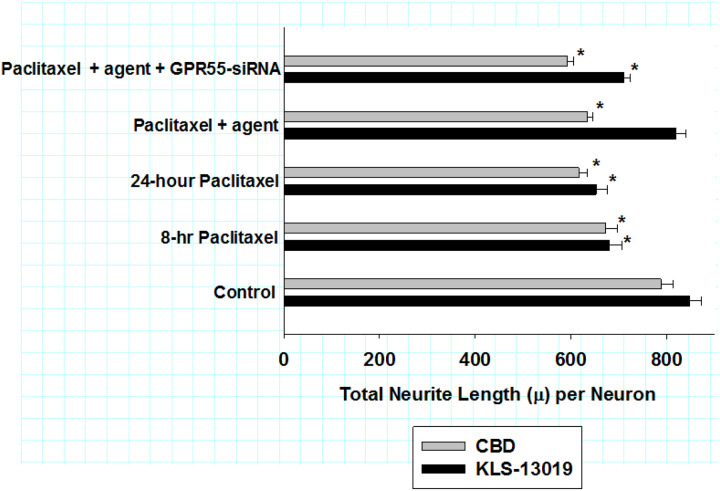

GPR55 knockdown and neuritic retraction

Within the high content analysis algorithm, general neuronal structures characteristics were also analyzed using beta-3 tubulin to identify DRG neuronal structure. These measures indicated that while there was no change in the total number of neurons or cell body areas after the various treatments (data not shown); however, there were significant effects on the total length of neurites per neuron in the day 9 DRG cultures at the termination of the reversal experiment. As presented in Fig. 5, the values for total neurite length per neuron are compared for both KLS-13019 (black bars) and CBD (grey bars) treatment using the reversal paradigm described previously. After the 24-hour treatment period, paclitaxel treatment produced a decrease the total neuritic length per neuron by 21–23% from controls. Treatment with 100 nM KLS-13019 resulted in neurite lengths per neuron that were not significantly different from that of controls. It is of interest that in cultures that had been co-treated with paclitaxel, KLS-13019 and GPR55 siRNA, there was an attenuation of the decreased neurite length by 65 ± 2% in comparison to cultures treated with KLS-13019 and paclitaxel. These studies indicate that pharmacological effect of KLS-13019 in reversing a decrease in neurite length could be attenuated by GPR55 knockdown (59 ± 6% of control). In contrast to the reversal effect of KLS-13019, there was no apparent change in total neurite length per neuron after treatment with 10 μM CBD in comparison to cultures treated only with paclitaxel. In addition, cultures treated with paclitaxel, CBD and GPR55 siRNA showed no change in total neurite length per neuron in comparison to that produced by CBD and paclitaxel. Together, these data indicate that KLS-13019, but not CBD, had an effect on reversing paclitaxel-mediated retraction of total neuritic length per neuron.